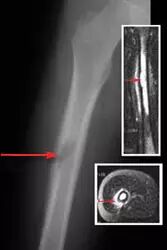

![]()

股骨(大腿骨)肿瘤。 这个x射线显示在大腿骨中间的肿瘤。还使用磁共振成像(MRI)观察肿瘤。顶部的插入物显示冠状MRI。底部的插入物显示横截面MRI。所有图像上的箭头显示肿瘤的位置